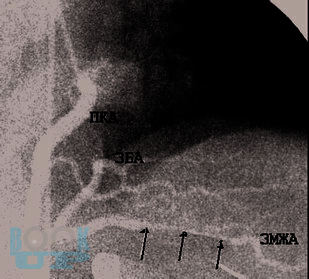

В пособии представлены особенности клиники и диагностики врождённой коронарной патологии – мышечного мостика, наличие которого при определённых условиях может стать причиной острого коронарного синдрома и внезапной сердечной смерти (на втором месте после гипертрофической кардиомиопатии) у молодых людей без факторов риска ишемической болезни сердца. Последовательно изложены возможности повышения информативности функциональной пробы с физической нагрузкой и стресс-эхокардиографии в выявлении ишемии миокарда, вызываемой коронарной аномалией. Далее показана эффективность медикаментозных средств, чрескожного вмешательства, хирургической коррекции у больных с мышечными мостиками.